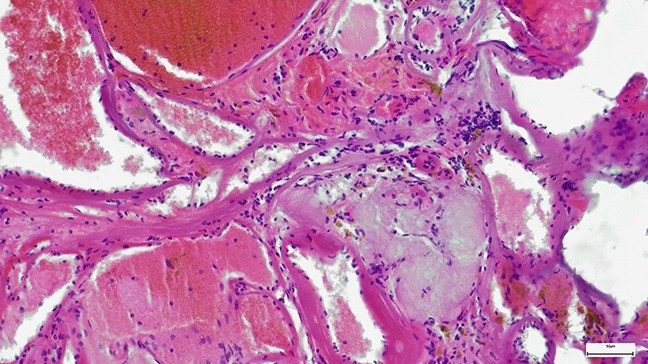

Adenoid cystic carcinoma is a rare cancer of the secretory glands, which are glandular tissues that make and release substances such as saliva, tears and sweat. It can develop throughout your body, but it is most common in the salivary glands in your head and neck.